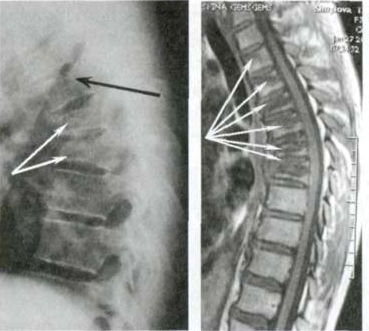

Podívejte se na tuto fotografii. Je to páteř člověka jen ve 44 letech, ale vypadá jako u starého člověka. Dříve se takové destrukce objevovaly po 60, dnes jsou běžné už u těsně nad 40. Tyto změny se s věkem zhoršují a jejich ignorování znamená riziko úplné ztráty pohyblivosti!

Páteř 44letého pacienta: vše začalo prostou bolestí, ale během týdne se objevila kýla, o dva týdny později posunutí obratlů, stlačení nervů a invalidní vozík.

Podívejte se na tyto fotografie. To se stalo těm, kdo příznaky ignorovali. Dnes jsou bezmocní a mnoho z nich nemá na koho se o péči spolehnout. Opravdu chcete takový osud?

Kýla meziobratlové ploténky, stlačení nervů, ztráta citlivosti a částečné ochrnutí nohou.